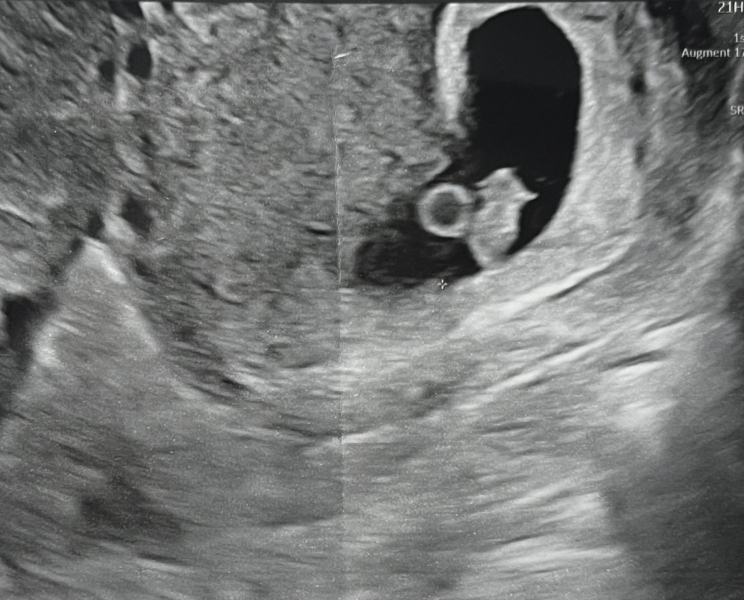

TinyDancer91 · 06/07/2024 23:10

Just a quick update for you all. We had our scan on Weds and have now officially been discharged from the clinic!! 🥳

We saw our little bean's heartbeat 💗

Due date has been estimated at 19th Feb. Still all feels like a dream! Luckily, I've not experienced any morning sickness yet (I have emetophobia) feeling very tired though.

Here's the first pic of our little bean.